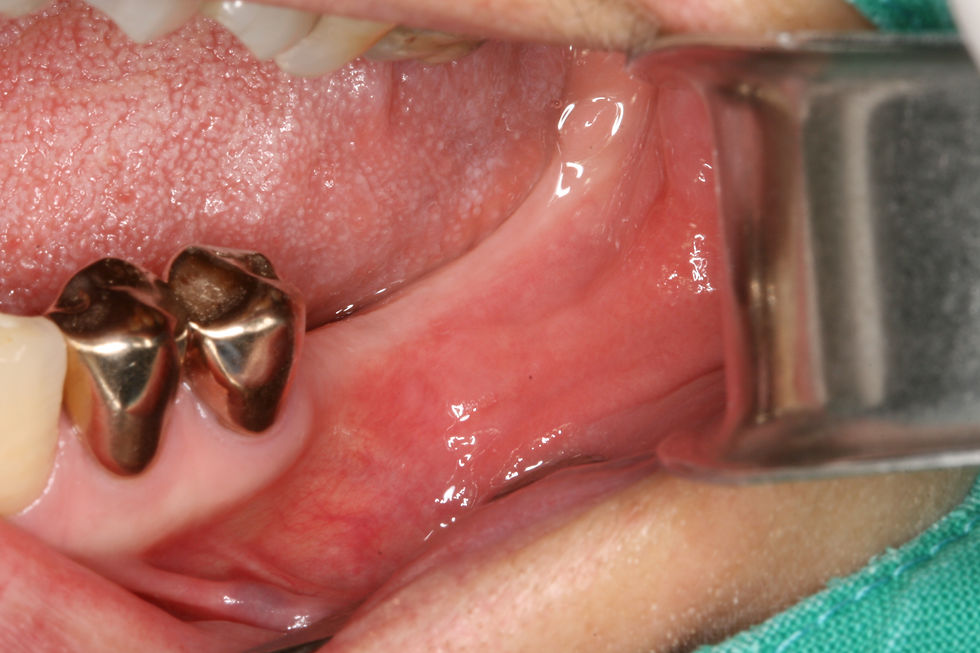

At the 1-month follow-up, patient visited for uncovery and soft tissue healing was observed with stable and healthy mucosal contours.

Flap elevation to uncover the implants during the second-stage surgery

Healing abutments were connected after implant uncovering